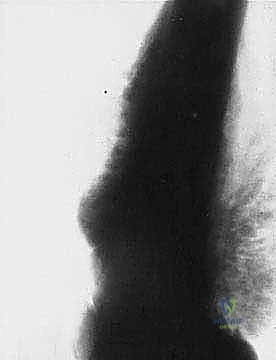

تتميز هذه الأورام بقدرتها على اختراق الأنسجة المجاورة وتكوين ما يُعرف بـ "المنطقة التفاعلية" (Reactive Zone) أو الكبسولة الكاذبة، والتي تحتوي غالباً على خلايا سرطانية مجهرية. هذا المفهوم البيولوجي هو ما يوجه الدكتور محمد هطيف في تحديد مدى الاستئصال الجراحي.

الهدف الأول في جراحة الساركوما ليس فقط إزالة الكتلة المرئية، بل استئصالها مع طبقة من الأنسجة السليمة المحيطة بها لضمان عدم ترك أي خلايا مجهرية. تُصنف الهوامش الجراحية إلى:

- الاستئصال داخل الورم (Intralesional): يتم قطع الورم من الداخل. غير مقبول في الساركوما الخبيثة.

- الاستئصال الهامشي (Marginal): الاستئصال عبر الكبسولة الكاذبة للورم. يحمل خطر عودة الورم (Recurrence).

- الاستئصال الواسع (Wide Resection): وهو المعيار الذهبي. يتم استئصال الورم مع طبقة من الأنسجة السليمة المحيطة به (العضلات، العظام). هذا ما يبرع فيه الدكتور هطيف لضمان الشفاء التام.

- الاستئصال الجذري (Radical Resection): استئصال كامل الحيز العضلي أو العظمي الذي يحتوي على الورم.

* العلاج الكيميائي قبل الجراحة (Neoadjuvant Chemotherapy): يُعطى لتصغير حجم الورم، مما يسهل عملية الحفاظ على الطرف، ويقتل الخلايا السرطانية الدقيقة المنتشرة في الدم.